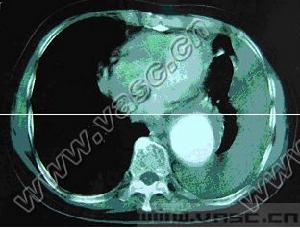

6.超聲心動圖:主動脈竇呈局限隆起,波形中斷,於舒張期脫人右心室流出道或右心房間隔下緣,二維可示破裂處,都卜勒證實分流。

主動脈竇動脈瘤破裂7.逆行升主動脈造影可確診,表現為動脈竇擴大畸形,右心室流出道和肺動脈或右心房有造影劑顯影。

主動脈竇動脈瘤破裂主動脈竇動脈瘤是一種罕見的先天畸形,約占先天性心臟病患病率的2%~3.56%,其破入右室者最多,其次為右房。發生原因主要是胚胎期竇壁中層彈力纖維發育不良,在主動脈內高壓影響下,該薄弱處逐漸變薄擴張,呈囊袋狀突出,當壓力突然增加時破裂,由於主動脈和破入心腔間存在著較大的壓力階差,可產生大量的左向右分流,因而導致全心容量負荷增加,特別是外破口較大或破入右房者,病情進展快,容易發生充血性心力衰竭,部分患者易繼發心內膜炎、心律紊亂、腎功能衰竭等嚴重併發症。臨床多表現為起病急、進展快。一般認為,主動脈竇動脈瘤破裂之前多無明顯症狀和體徵,一旦破裂,即產生劇烈胸痛及顯著的血流動力學改變。破入右室、右房者可出現右心衰竭,呈進行性加重。體徵有胸骨左緣第3、4肋間連續性響亮機器樣雜音,常伴有肺動脈高壓、右心功能不全及脈壓差增大的表現。首次聽診往往有主動脈瓣受損的印象,易誤診為主動脈瓣關閉不全,本例即是此種情況。超聲心動圖是最佳的無創診斷法,可直接顯示主動脈竇動脈瘤的起源形態、突入的心腔位置、竇瘤破口大小、是否合併其他心臟畸形、分流的性質、時相、最大流速,提供血流動力學資料。一旦瘤體破裂,預後不良,可在數周至數月內因嚴重併發症死亡。內科治療只能起到短暫的減輕作用,手術治療往往可以獲得滿意的效果。該戰士因沒有及時手術,導致急性腎功能衰竭並時間過長,多臟器衰竭而死亡。